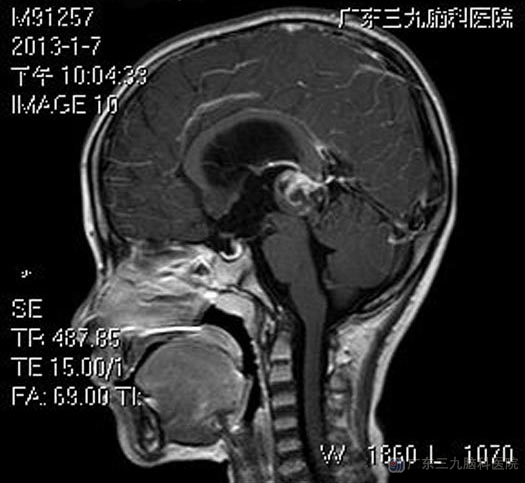

当地医院头颅CT检查提示松果体区占位,梗阻性脑积水。广东三九脑科医院头颅MR显示肿瘤大小约23.8mm×22.1mm×20.9mm,腰椎穿刺检查测得初压200 mmH2O(儿童正常值50-100mmH20)。

▲术前MR